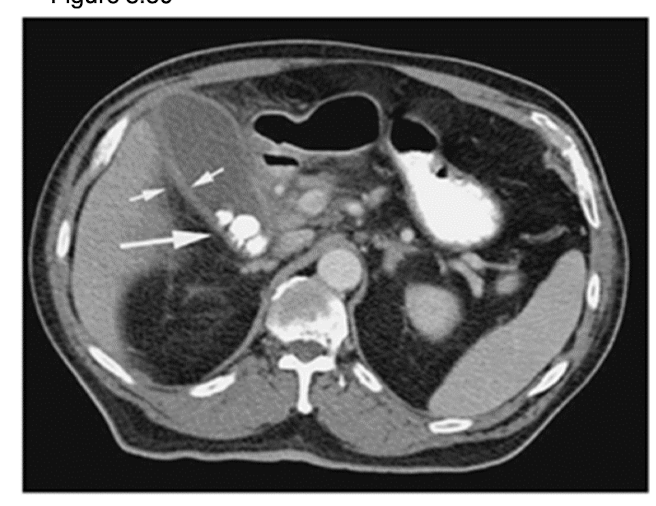

What is the investigative method of choice for evaluating the biliary system?

ultrasound